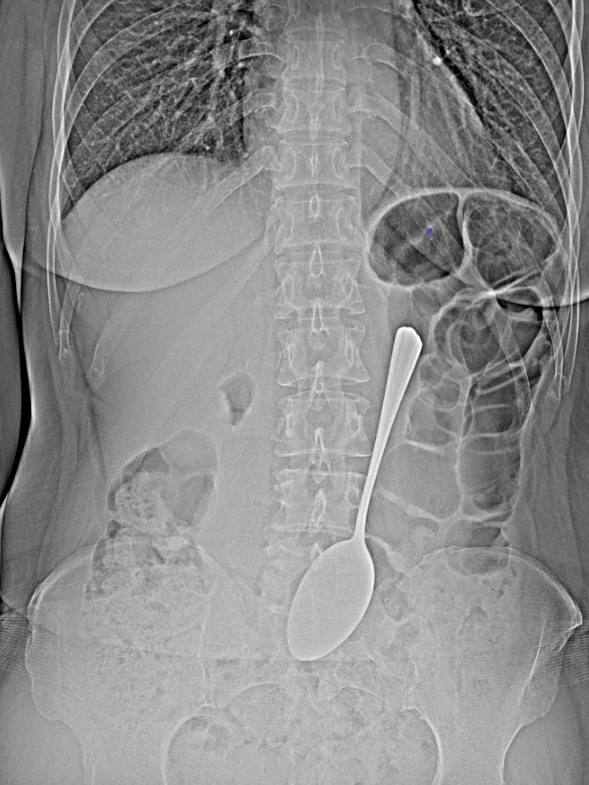

Жительница Бурятии проглотила столовую ложку

В Улан-Удэ врачи БСМП имени Ангапова оказали помощь пациентке, проглотившей столовую ложку. Медики извлекли металлический предмет из желудка с помощью эндоскопического оборудования, что позволило избежать сложной операции. После процедуры пациентку отпустили домой. Причину своего поступка она так и не назвала.

Как пояснили специалисты, крупные инородные предметы опасны возможными повреждениями желудка и кишечника. Если мелкие вещи, например монеты, иногда выходят самостоятельно, то в этом случае последствия могли быть серьёзными.